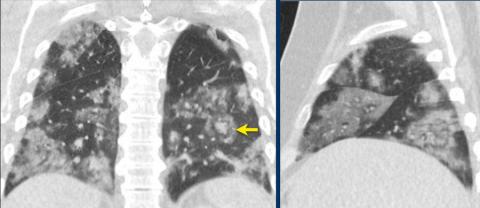

The following CXR is highly suggestive of what pulmonary pathology? _____

CO-RADS _____ (very high level of suspicion for pulmonary involvement by COVID-19 based on typical CT findings)